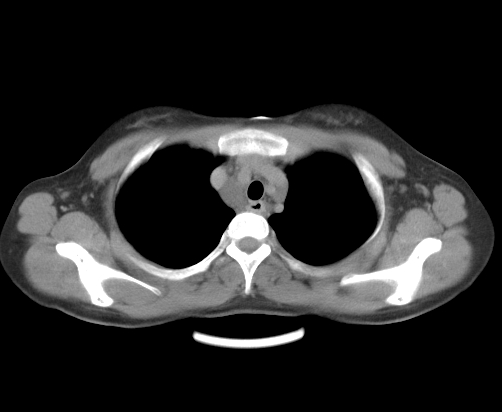

胸部